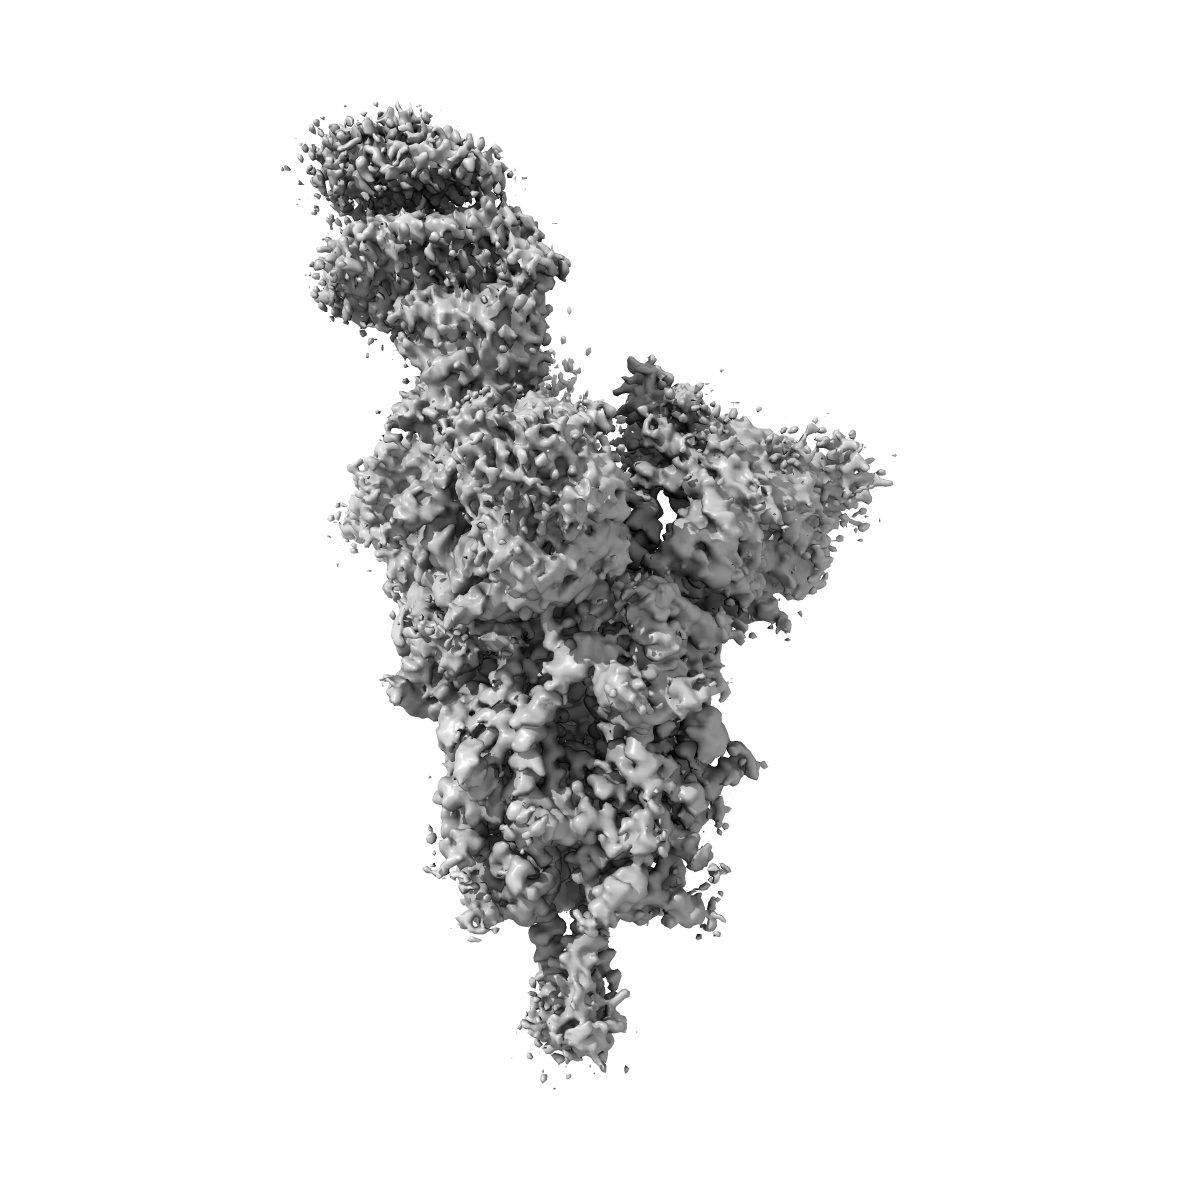

Cryo-EM structure of the SARS-CoV-2 D614G,L452R mutant spike protein ectodomain bound to human ACE2 ectodomain (global refinement)

Sample: SARS-CoV-2 D614G,L452R mutant spike protein ectodomain bound to human ACE2 ectodomain

Structural analysis of receptor binding domain mutations in SARS-CoV-2 variants of concern that modulate ACE2 and antibody binding.

Mannar D, Saville JW , Zhu X , Srivastava SS , Berezuk AM, Zhou S, Tuttle KS, Kim A, Li W, Dimitrov DS, Subramaniam S

(2021) Cell Rep , 37 , 110156 - 110156